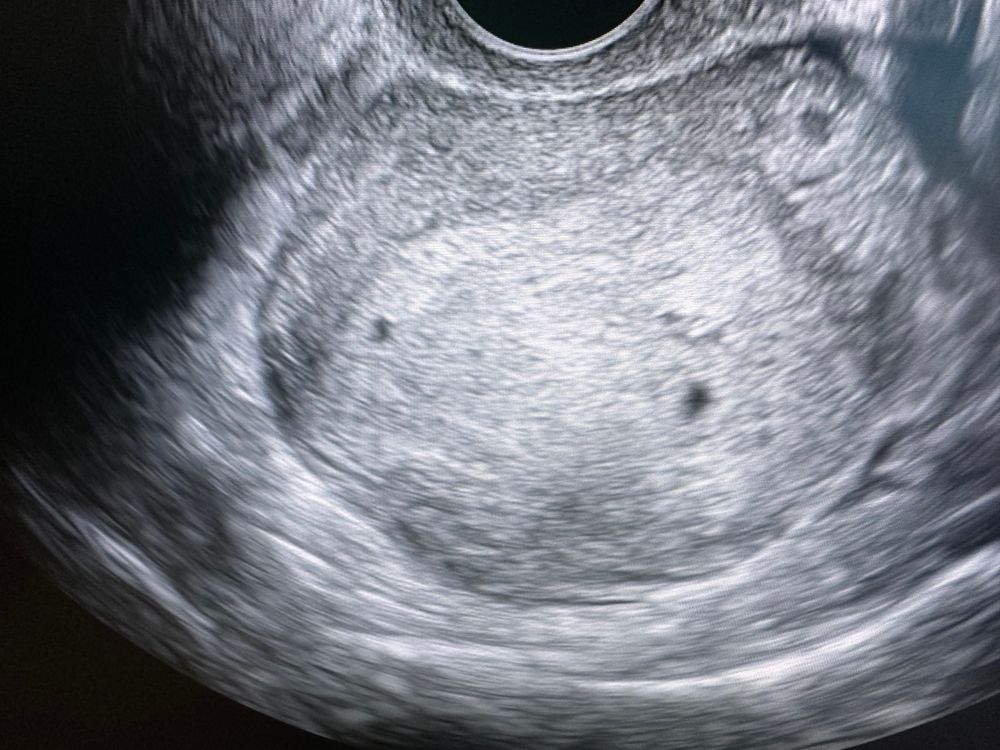

Была сейчас на узи, врач сказала, что матка большая для моего срока. В матке одно плодное яйцо нормальных размеров, второе под вопросом меньше в 2 раза. Что думаете? У кого-то было подобное? Теперь не знаю что думать